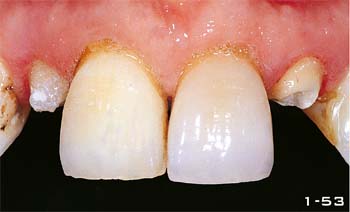

Abb. 1-53 Nur nach ausreichendem Bleichen können die lateralen Schneidezähne mit Fiberglasstiften und -Aufbauten versorgt werden.